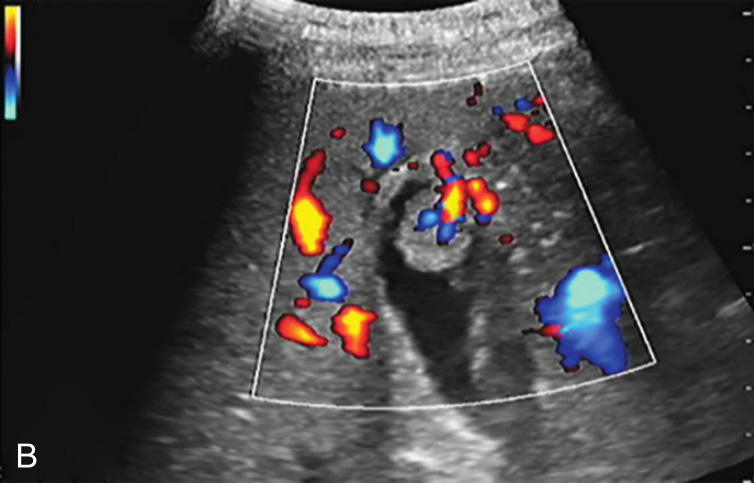

图2-3-2 腺瘤样性息肉常规超声图像

A.胆囊体部单个结节状中等回声,内部回声欠均匀;B.病灶内部分支状血流信号

对于较小的息肉,CDFI一般无明显血流显示。较大的息肉或腺瘤性息肉,CDFI可显示点状或从底部进入的细条状动脉血流。

腺瘤性息肉应与息肉型胆囊癌鉴别。后者形态不规则,内部回声不均匀,表面回声模糊、欠光滑,基底部较宽,胆囊壁层次不清,黏膜层高回声不连续;病灶内部见粗大且不规则的血流信号;超声造影呈快进快退,内部可见粗大树枝状血管,胆囊壁层次不清。